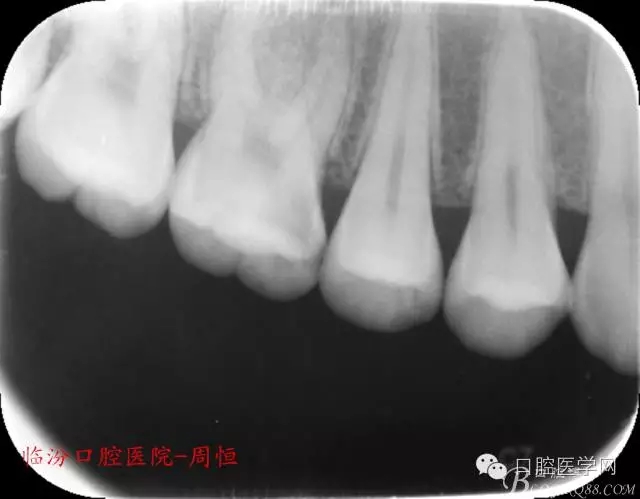

檢查:16近中齲壞深,探痛,已露髓,冷測痛明顯,叩痛(+-),無松動(dòng)全口牙石(++),牙齦紅腫。

X 示:近中低密度陰影達(dá)髓腔,牙根未見異常。

圖1 X示 術(shù)前